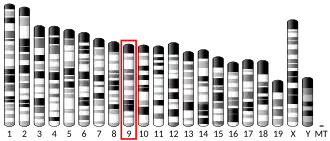

Genetics

Allelic variants:

- A-241G

- C132T, G423A, T765C, C939T, C957T, and G1101A[25]

- Cys311Ser

- -141C insertion/deletion[26] The polymorphisms have been investigated with respect to association with schizophrenia.[27]

Some researchers have previously associated the polymorphism Taq 1A (rs1800497) to the DRD2 gene. However, the polymorphism resides in exon 8 of the ANKK1 gene.[28] DRD2 TaqIA polymorphism has been reported to be associated with an increased risk for developing motor fluctuations but not hallucinations in Parkinson's disease.[29][30] A splice variant in Dopamine receptor D2(rs1076560) was found to be associated with limb truncal tardive dyskinesia and diminished expression factor of Positive and Negative Syndrome Scale (PANSS) in schizophrenia subjects.[31]